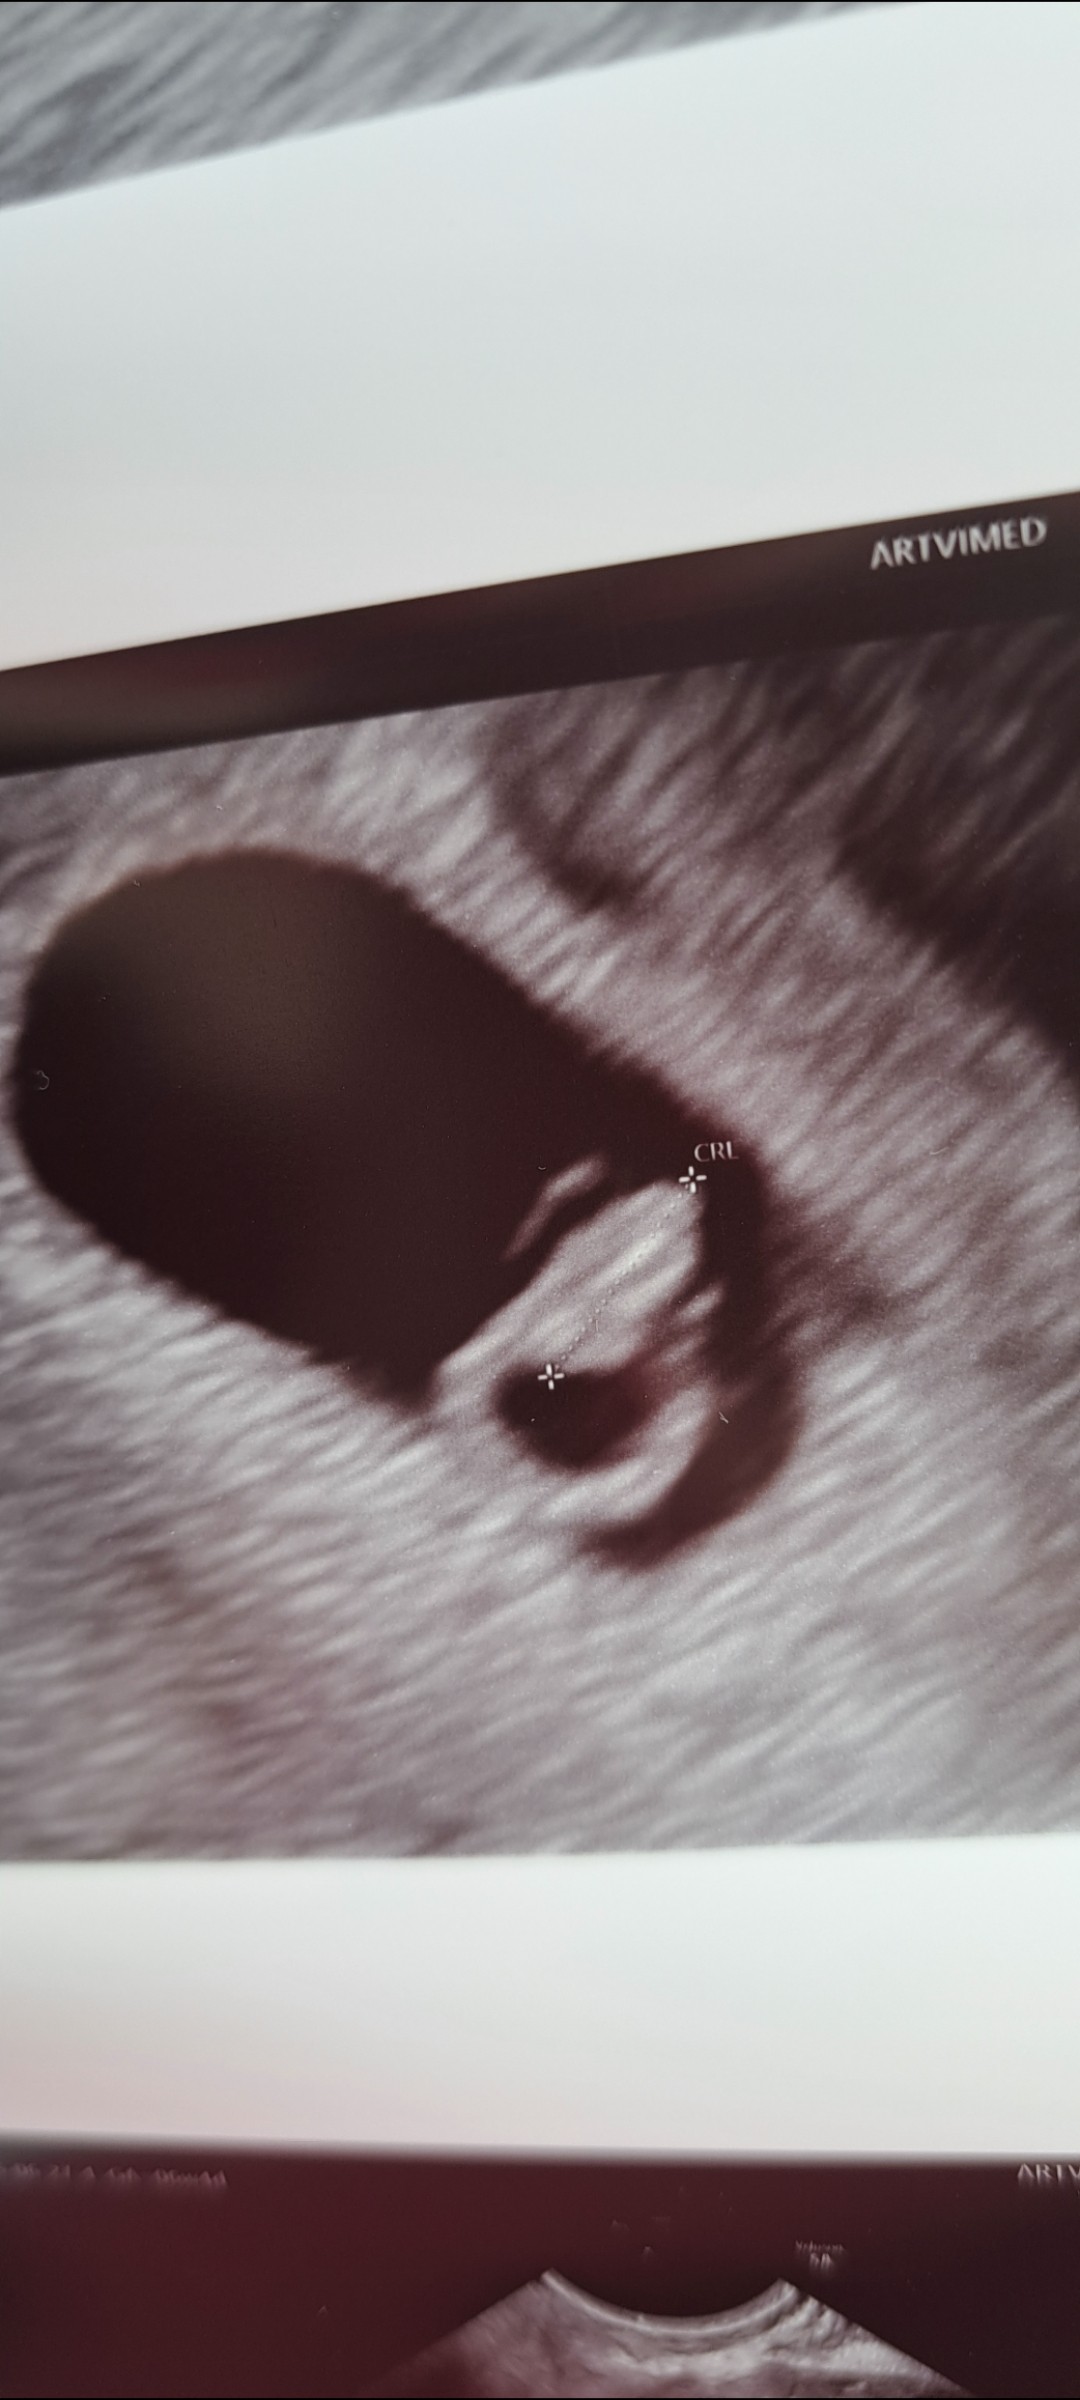

Przedstawiam wam moją kruszynka 🥹

Załączniki

• Screenshot_20250627_202138_Gallery.jpg

Screenshot_20250627_202138_Gallery.jpg

254 KB · Wyświetleń: 68